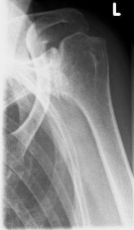

left: X-ray image of an omarthrosis

right: X-ray of a healthy shoulder joint

X-rays can be used to reliably diagnose the extent of joint wear. In the case of severe osteoarthritis, for example, the joint space and the formation of jagged edges (osteophytes) can be detected. If additional damage to the tendons of the shoulder (rotator cuff) is suspected, ultrasound examination (sonography) or magnetic resonance imaging (MRI) can help clarify the situation.